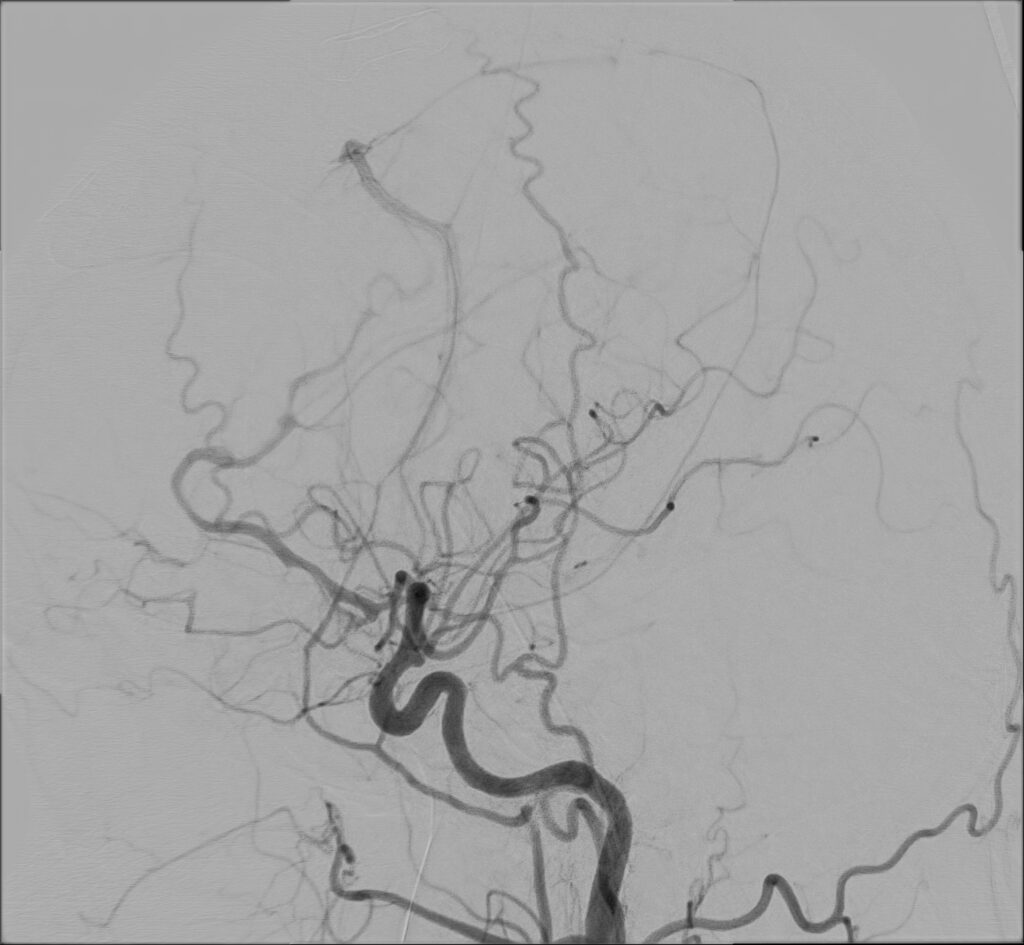

W przypadku prezentowanej pacjentki nie stwierdzono objawów neurologicznych poza bólem głowy. Po wstępnej diagnostyce została przekazana do Oddziału Neurochirurgicznego Szpitala Kopernika w Łodzi. W trybie pilnym wykonano angiografię cyfrową (DSA), która precyzyjnie uwidoczniła AVM.

Przeprowadzono embolizację części tętnic zaopatrujących AVM, co zmniejszyło ryzyko krwawienia śródoperacyjnego. Następnie wykonano kraniotomię podpotyliczną lewostronną z całkowitym usunięciem malformacji. Zabieg przebiegł bez powikłań, po zabiegu u pacjentki nie stwierdzono deficytów neurologicznych. Kontrolna angiografia potwierdziła całkowite usunięcie zmiany, co pozwala uznać pacjentkę za wyleczoną.

W badaniu angiografii subtrakcyjnej widoczne jest rozległe (ponad 3 cm) gniazdo naczyniowe zaopatrywane z tętnicy przedniej mózgu prawej, zarówno z gałęzi okołospoidołowej, która oddawała 2 tętnice żywiące, jak i gałęzi korowych, oddając jedno naczynie żylne drenujące do zatoki strzałkowej górnej.